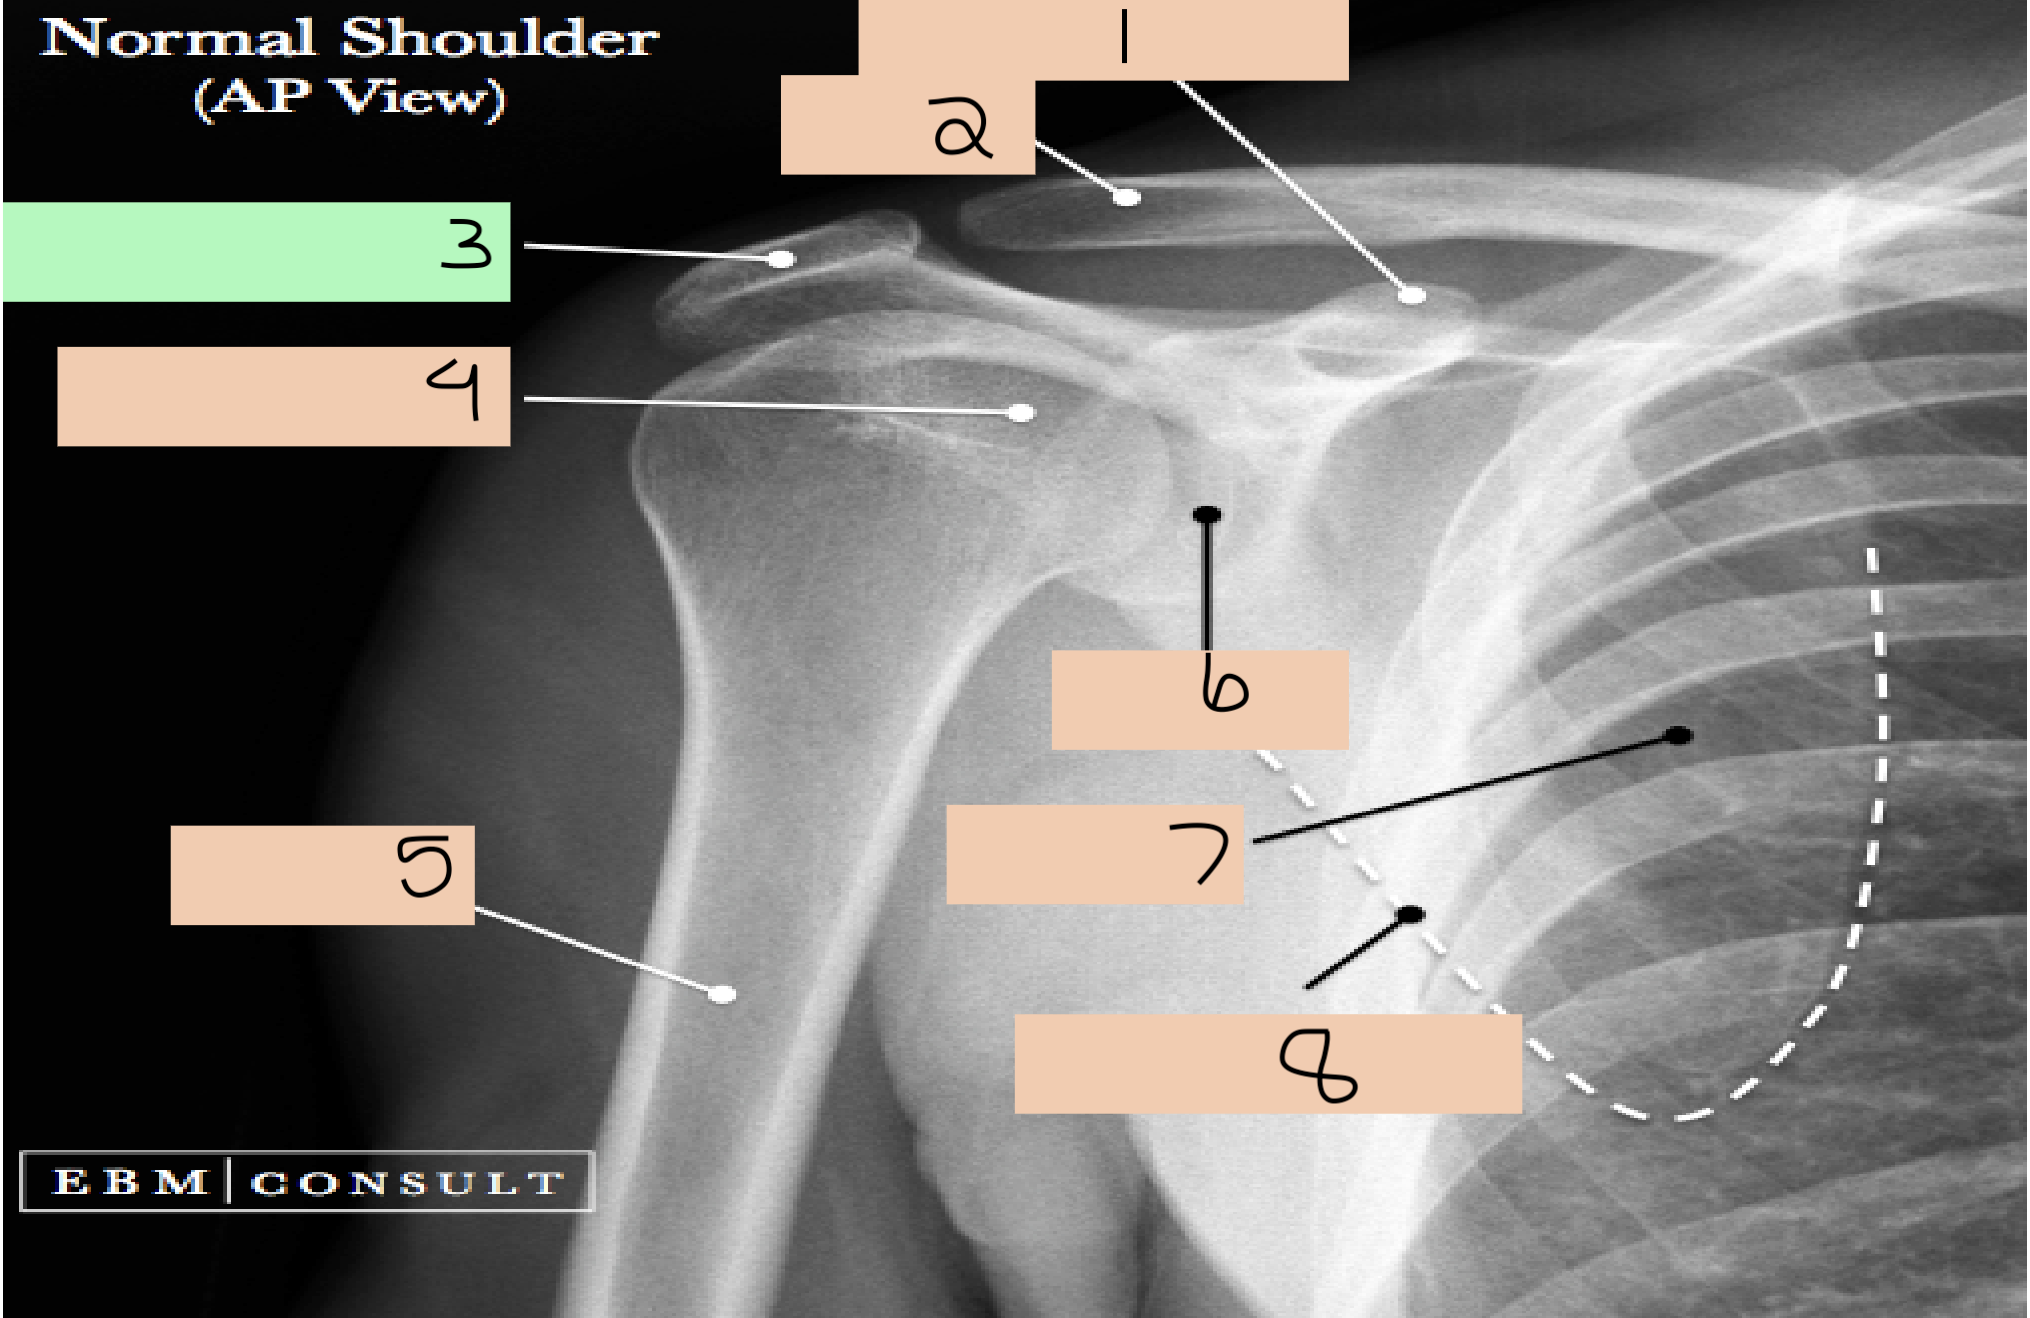

1

coracoid process

2

clavicle

3

acromion process

4

humeral head

6

glenoid

7

body of scapula

8

lateral border of scapula